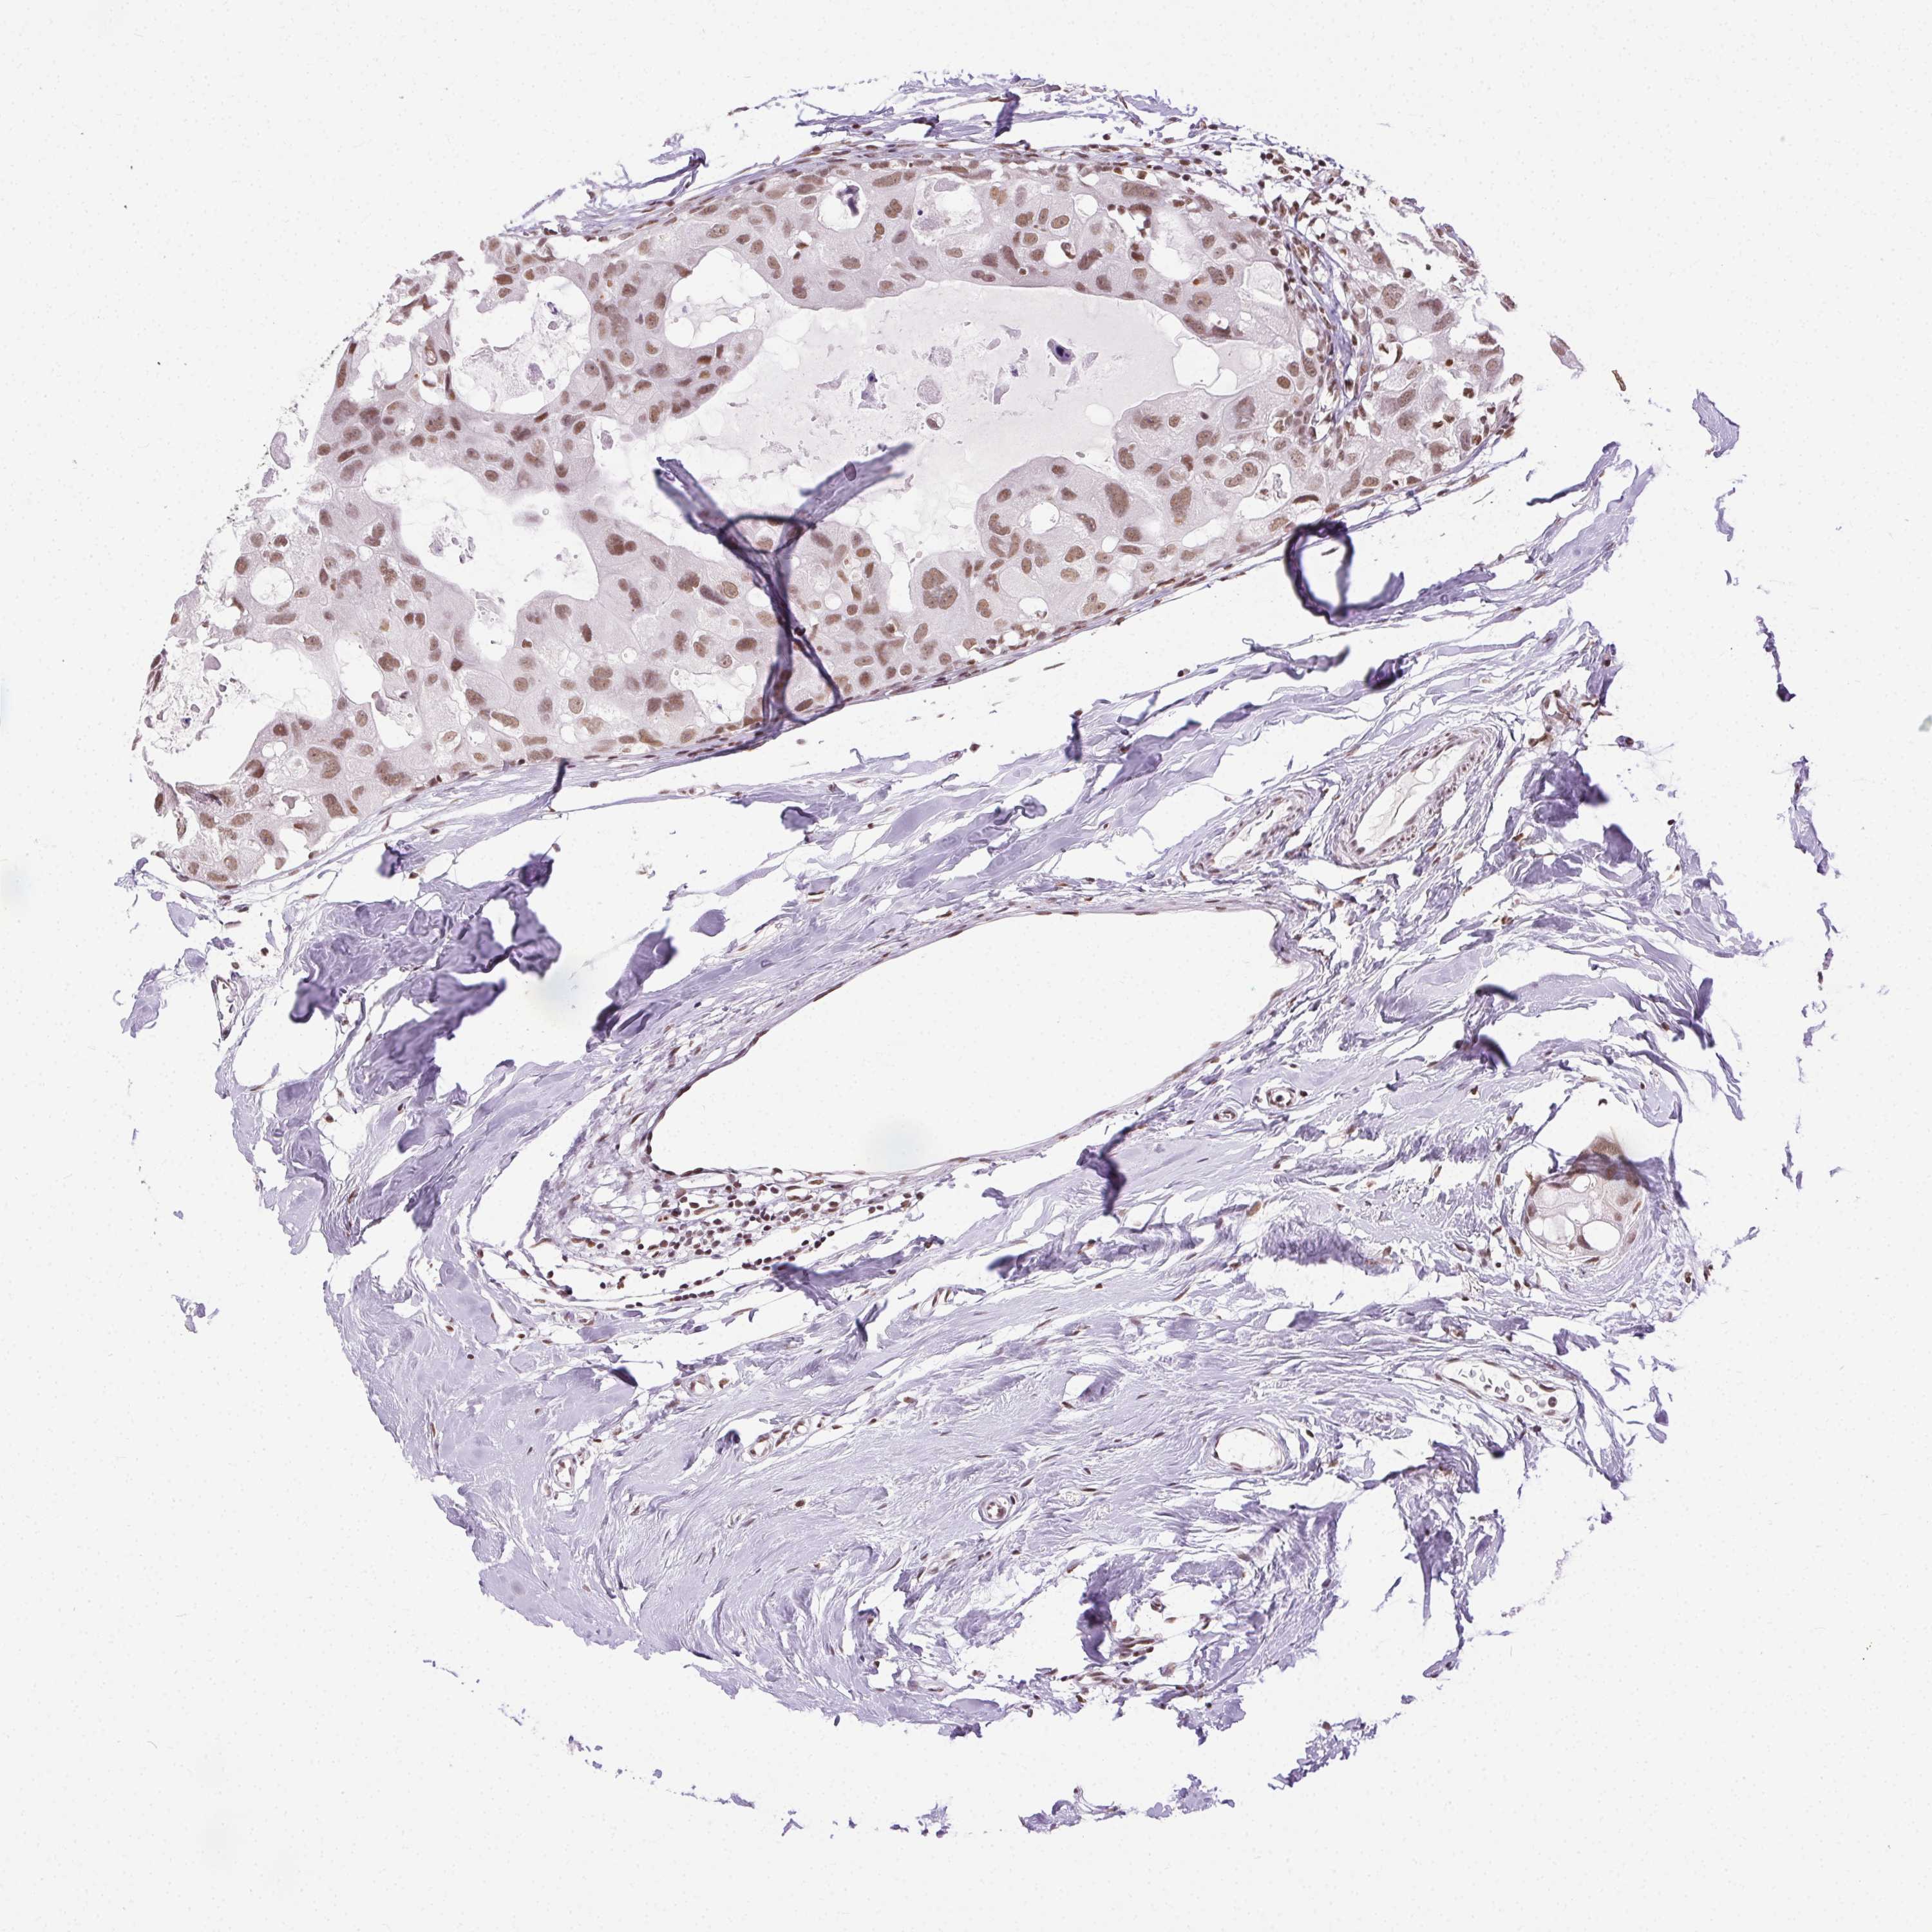

CANCER BREAST CANCER Show tissue menu

BRCA TCGA BRCA VALIDATION PROTEIN EXPRESSION